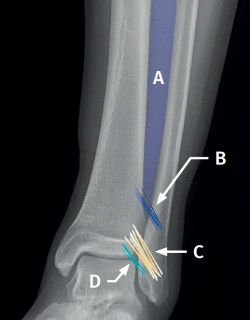

Syndesmosis (Figure 1)

Figure 1. Schematic representation of the anterior syndesmosis. A: interosseous membrane; B: interosseous ligament; C: anterior tibiofibular ligament; D: distal fascicle of the anterior tibiofibular ligament.